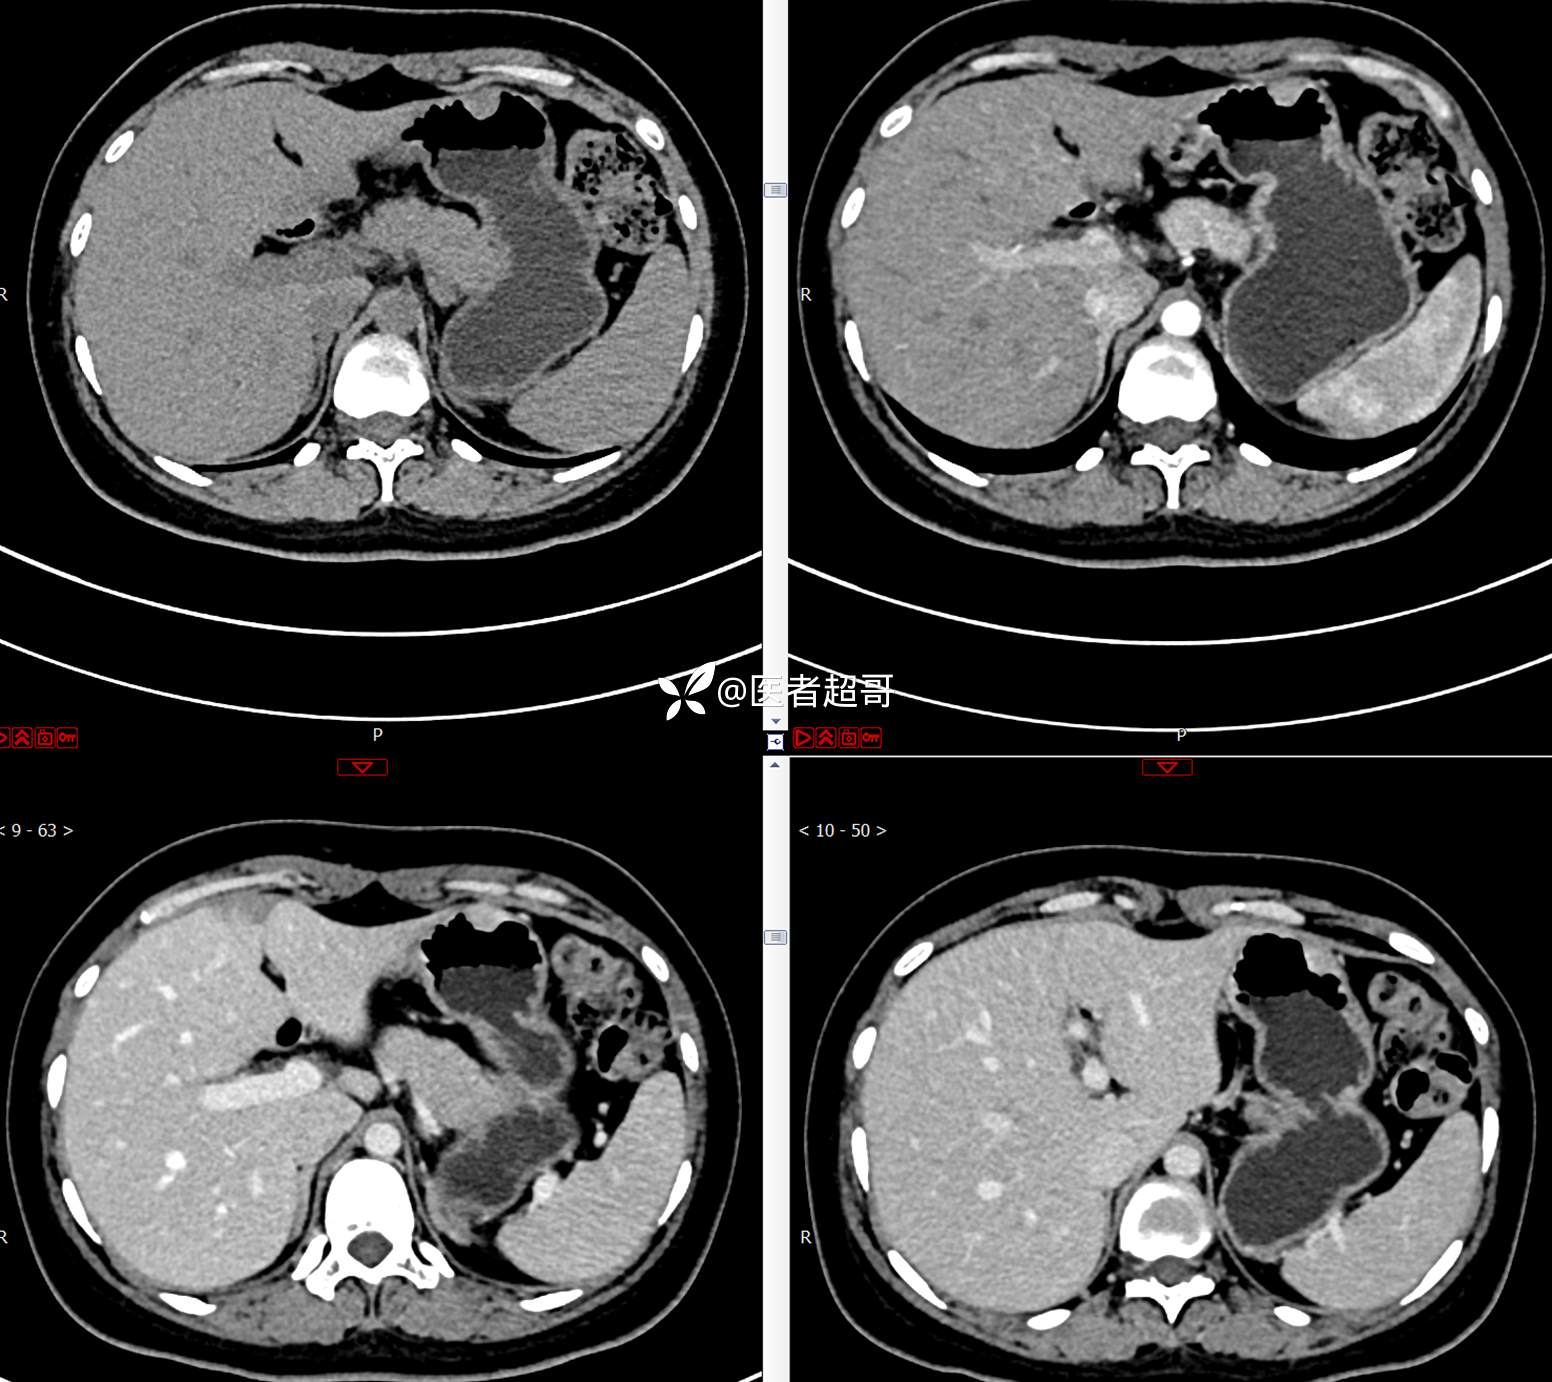

青年男性,恶心、呕吐5年,发现胃肿物3月,有结果,请分析!

主 诉:恶心、呕吐5年,发现胃肿物3月。

现病史:患者5年前无明显原因及诱因出现恶心、呕吐,多于进食后出现,呕吐物为胃内容物,无鲜血及咖啡样物质,偶有空腹痛,无放射痛,无腹泻,无便秘,无黑便、鲜血便,无胸闷、心慌,无头痛、头晕,曾就诊于当地医院口服“消炎药”治疗(具体不详),上述症状反复出现,3月余前就诊于市第二人民医院,行胃肠镜检查:慢性浅表性胃炎、胃体粘膜下占位,后就诊于我院超声内镜检查:胃体肿物,似来源于黏膜下层,今为行进一步治疗来我科就诊,门诊以“胃肿物”收住入院。患者自发病以来,神志清,精神可,饮食一般,睡眠可,大小便正常,体重无明显变化。